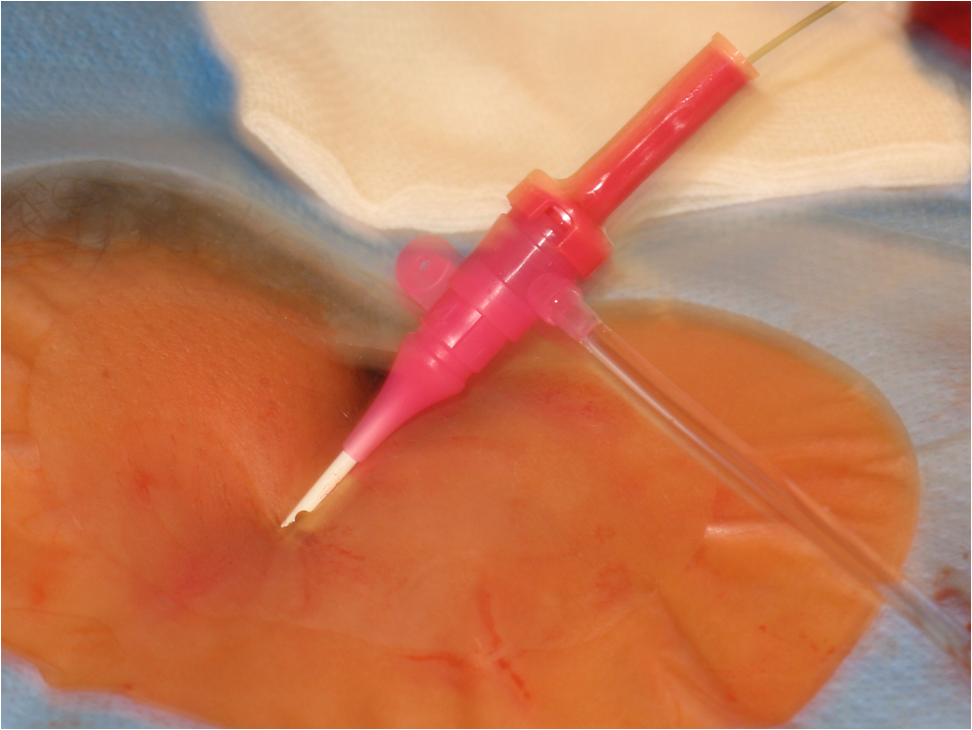

Seldinger technique is used for vascular access. Arterial puncture by a Seldinger needle (Fig 1, Upper row, left panel) is most often pulse-directed (by palpation), but can be accessed by ultrasound guidance. Most commonly used access sites are common femoral and brachial arteries, radial arteries are used mostly by cardiologists, popliteal artery can be rarely punctured in special cases (retrograde recanalisation of superficial femoral artery occlusion). A guidewire is inserted into the needle (Fig 1, Upper row, right panel), the needle is withdrawn (Lower row - left panel) (at this point the puncture site should be compressed to prevent bleeding); a few mm dissection may be done by a scalpel, the introducer sheath and then a catheter is fed onto the guidewire (Lower row - right panel); then the guidewire can be withdrawn and contrast medium can be inserted through the catheter. More information on contrast medium is available in chapter 7.

Figure 1.: Seldinger technique. Upper row – left panel: one-part Seldinger needle; Upper row – right panel: the femoral pulse was well palpable, the right common femoral artery was punctured using the Seldinger needle, then the guidewire was inserted into the needle. Lower row – left panel: the needle was withdrawn, manual compression was performed to prevent puncture site hematoma; Lower row - right panel: a 4F introducer sheath was inserted onto the guidewire. Contrast medium can be injected through the sheath.